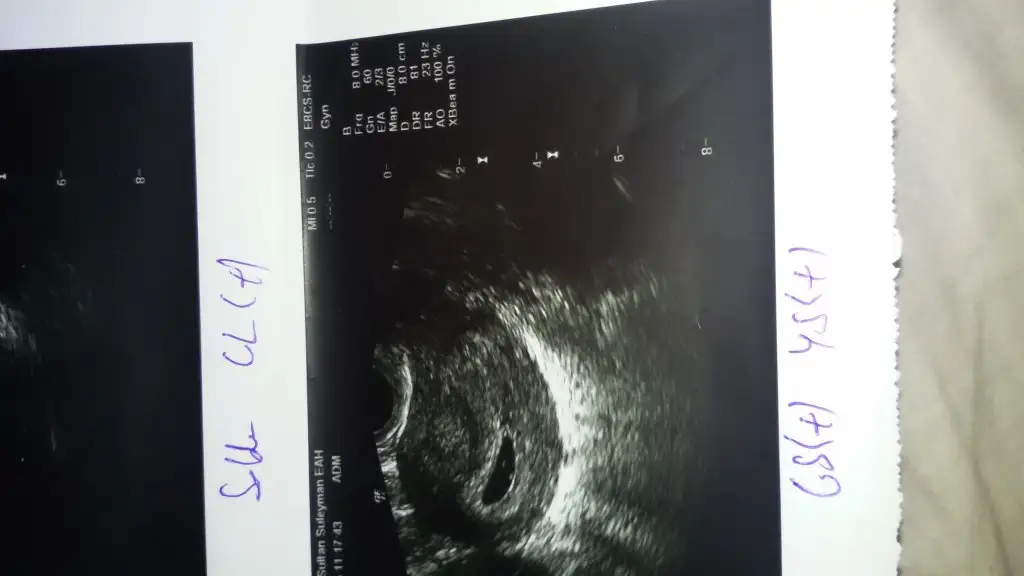

kızlar gunaydınnn.ben cuma doktora gıttıgımde 5 haftalık hersey normal dedı gonderdı.bır hafta sonra gel dedı sadece kesesını gordum kalbını duyamadım bana ultrason cıktısını verdı bende heyecandan dr hersey norml dıyınce kesenın ebatını soramadım. resım ekte ınceleyebılırmısınız belkı ıcınde yazıyordur ben anlayamadım ılk gebelık oldugu ıcın :)

GS karşısında kese boyutu yazması lazım ama yazmıo cnm